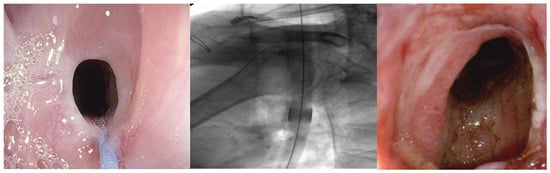

3.4. Endoscopic Stents

3.4.1. Fully Covered-Self Expandable Metal Stents (FC-SEMSs)

3.4.2. Biodegradable Stents (BDSs)

3.4.3. Lumen-Apposing Metal Stent (LAMS)